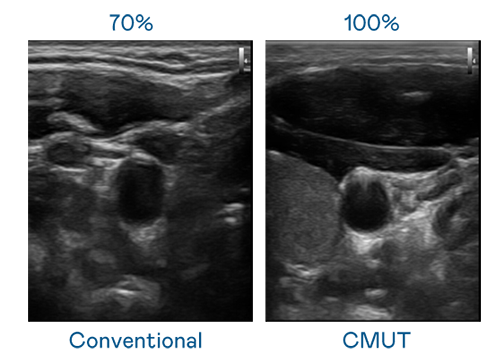

CMUT 技术是一种用电容式微机电元件来产生超音波讯号的技术。与传统 PZT 压电式技术相比,CMUT 频宽增加 30%,更宽频的超音波讯号让影像解析度大幅提升,是实现高影像品质医疗超音波扫描、促进精准医疗发展的关键技术。

大频宽带来超清晰影像

超音波影像的解析度高低,首先取决于探头能发出的讯号频宽。九游会 CMUT 可提供高清晰的超音波讯号,提供高频宽、高灵敏度、影像纹理细节更高的超音波影像,协助医护人员缩短影像判读时间及利用精准的医疗影像进行诊断。